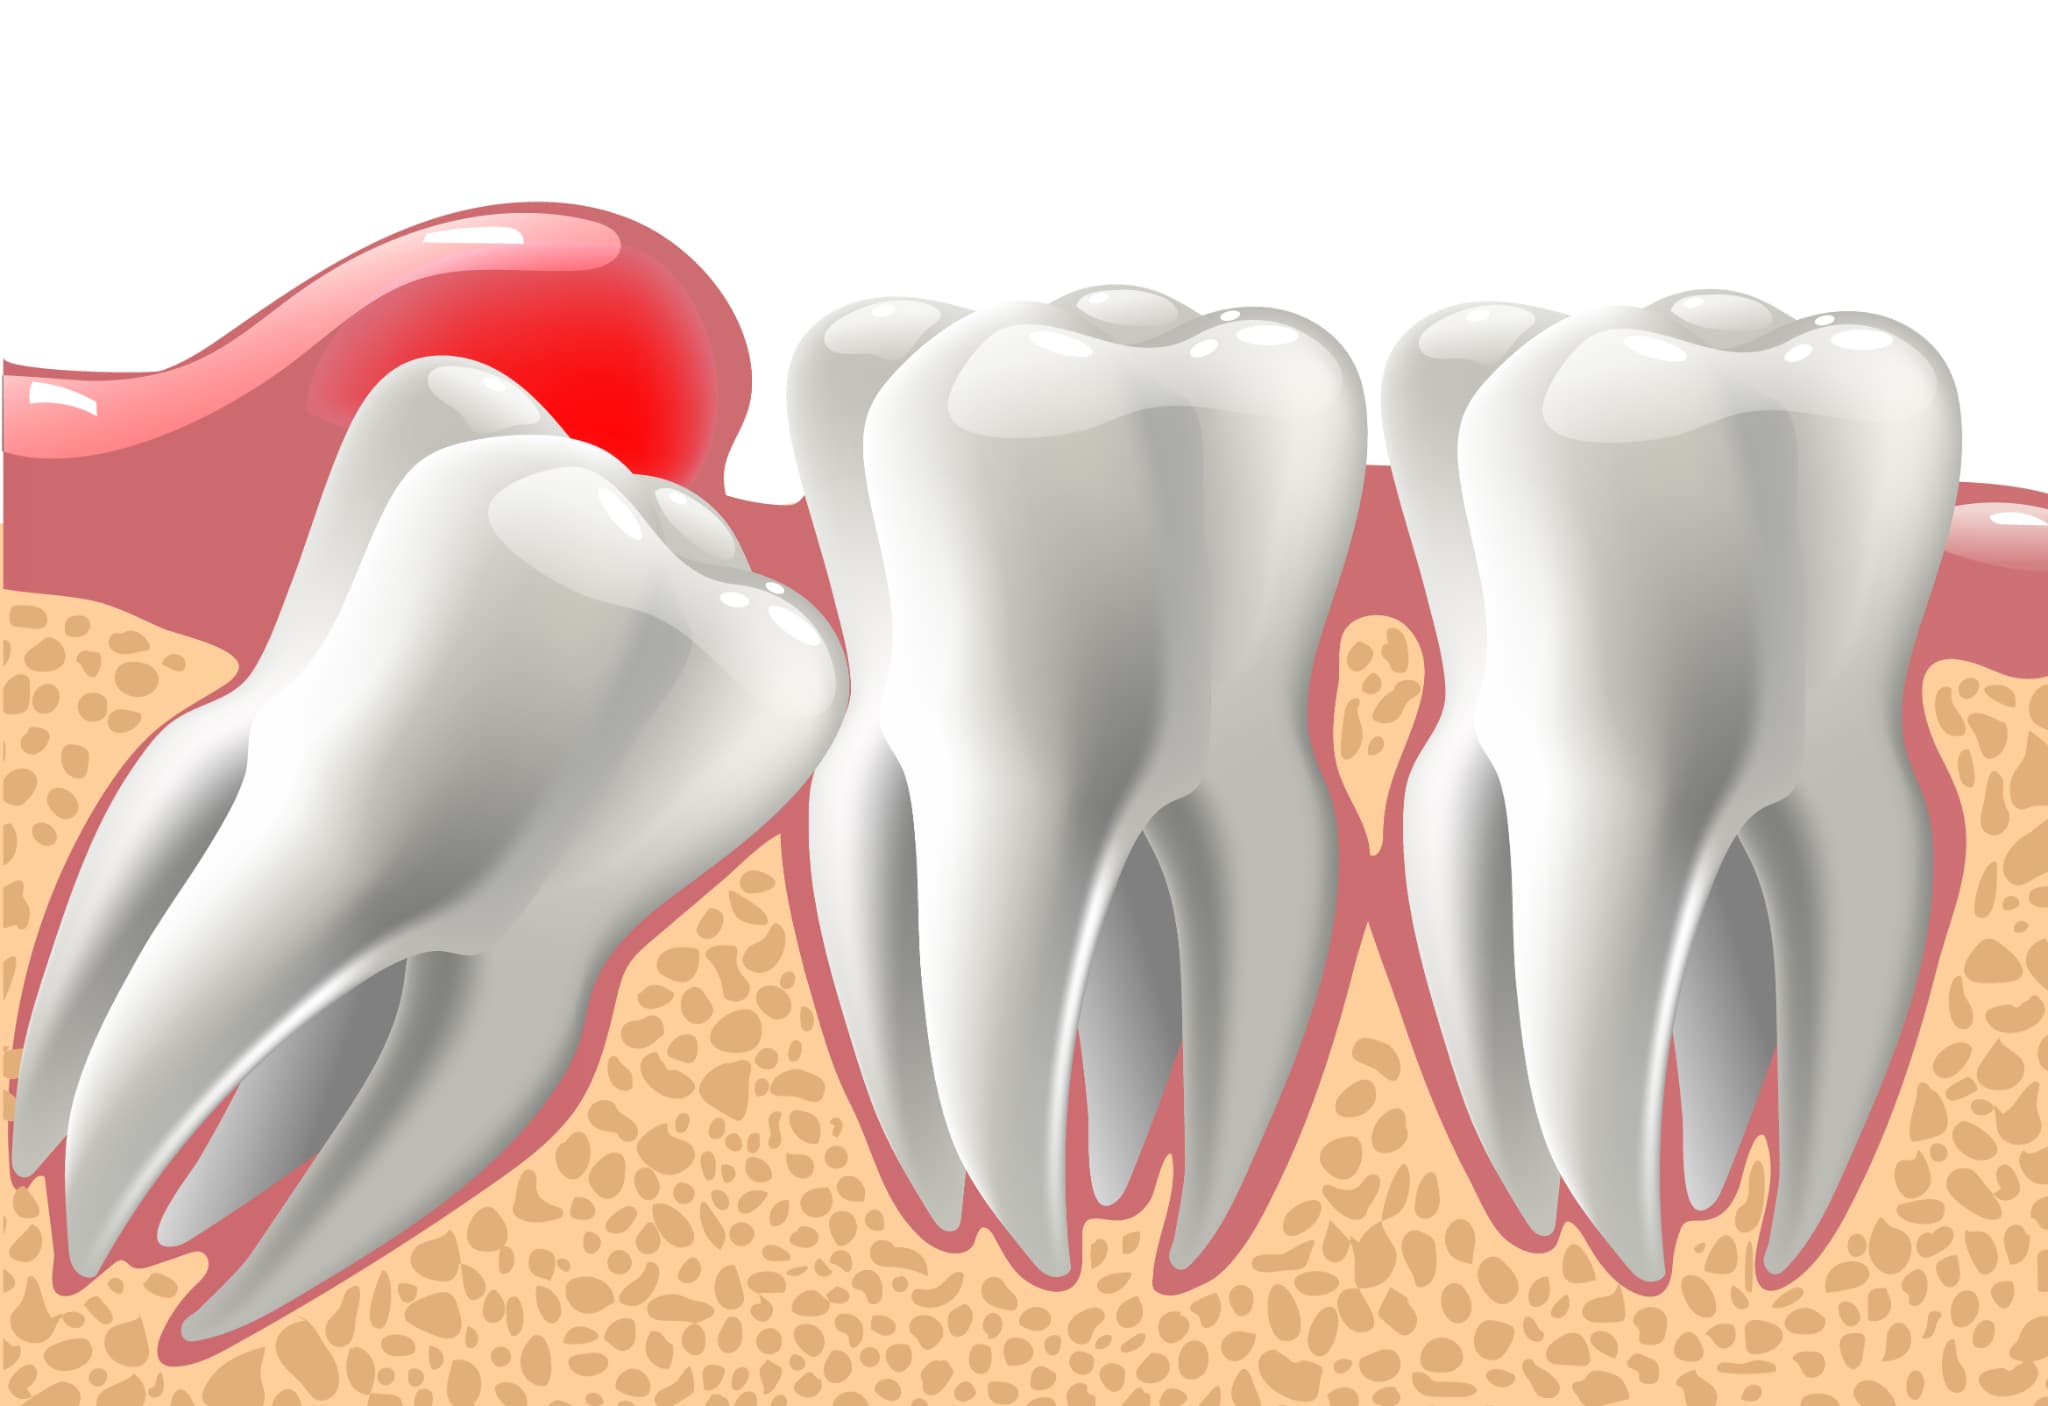

埋まっている親知らずが横向きや斜めの状態で存在している場合、手前の歯に強く接触していることがあります。この状態が長く続くと、隣の歯の根が少しずつ溶けるように吸収されることがあります。これを歯根吸収と呼びます。

歯の根は歯を支える大切な部分ですが、歯根吸収が進むと歯の安定性に影響が出ることがあります。初期の段階では自覚症状がほとんどないことが多く、気づかないまま進行することも少なくありません。

歯根吸収はレントゲン検査によって発見されることが多いため、親知らずが埋まっていると指摘されている場合は、定期的に歯科医院で状態を確認してもらうことが重要です。

埋まっている親知らずは、歯並びや噛み合わせに悪影響を与えることがあります。特に横や斜め向きに生えている場合、隣接する第二大臼歯を押す力が働き、前歯を含めた全体の歯列が少しずつずれることがあるのです。

また、矯正治療を受けて歯並びがきれいに整っている場合でも、親知らずの圧力によって後戻りを起こす可能性もあるでしょう。そのため、将来的な歯並びの乱れを防ぐ目的で抜歯を勧められるケースも少なくありません。